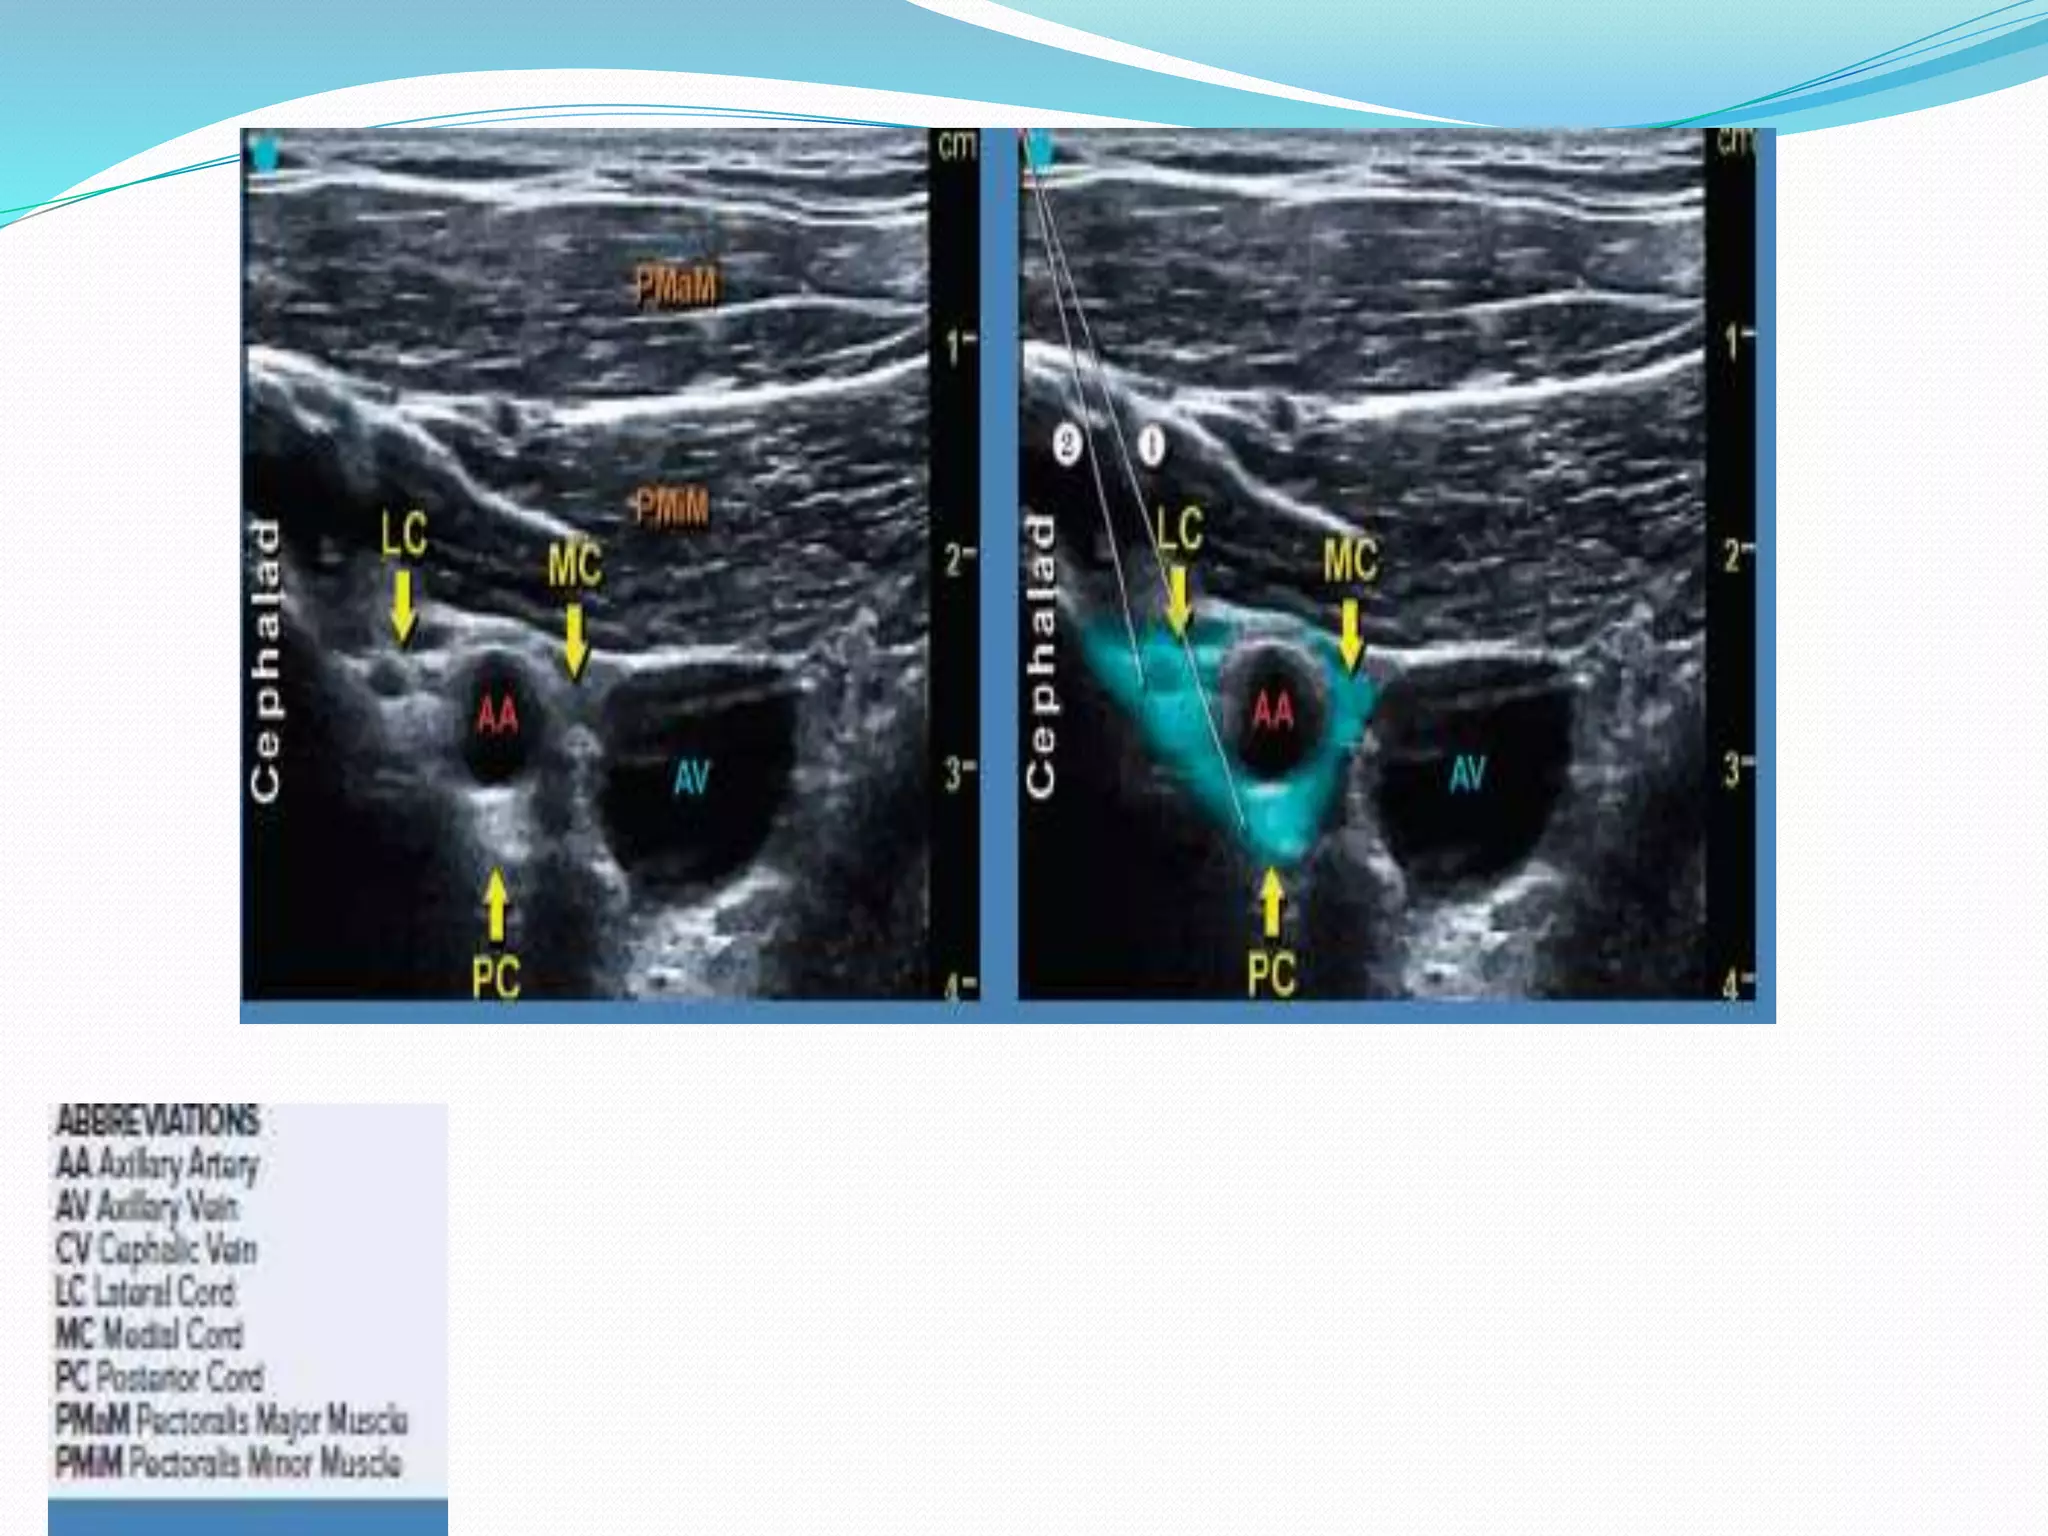

This document provides an overview of brachial plexus anatomy and techniques for brachial plexus nerve blocks. It begins with a description of the brachial plexus formation from cervical and thoracic nerve roots and its branching pattern. Four main approaches for brachial plexus nerve blocks are described: interscalene, supraclavicular, infraclavicular, and axillary. Details are provided on the anatomy and techniques for performing interscalene and supraclavicular brachial plexus blocks. Ultrasound guidance is discussed as an advancement which allows real-time visualization of needle and nerve. Complications are also summarized.